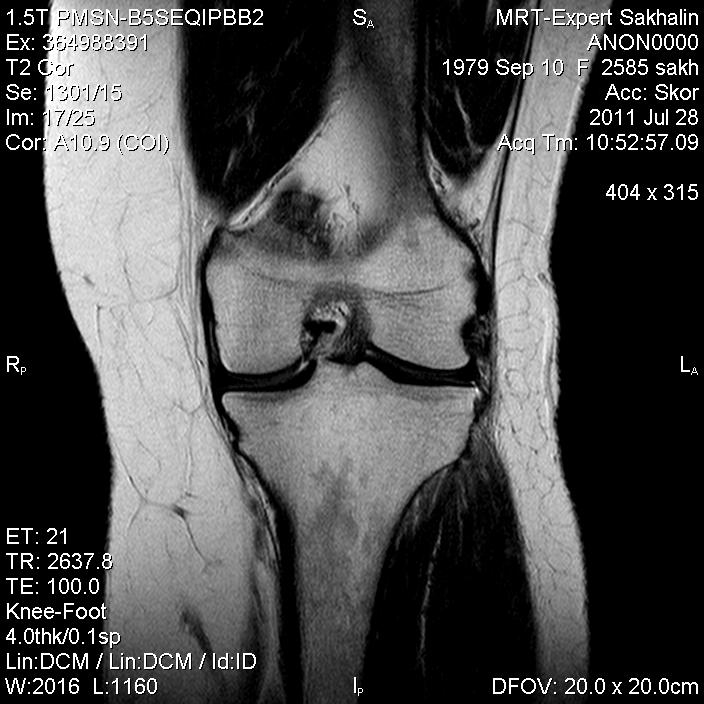

Коленный сустав

Подглядела случай у коллеги.

Что это может быть?

Не вижу криминала. А на что жалуется девушка?

P.S. В костях - это, скорее всего, резидуальный красный костный мозг.

участки гемопоэтического костного мозга